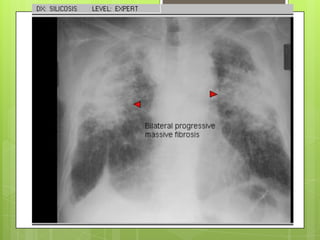

SILICOSIS

 CRÓNICA

 Tras 10 años de exposición continua con

concentraciones bajas

 AGUDA

 Luego de exposiciones intensas, luego de

semanas o menos de 5 años. Mal pronóstico.

 ACELERADA

 Entre 2 a 5 años después de exposición intensa,

con un alto potencial de formar fibrosis masiva

progresiva

 Datos clínicos no son específicos.

 Formas leves no causan síntomas

 En etapas avanzadas: tos (primero) y disnea

Rx tórax:

 Formas simples nódulos redondeados densos

de 1.5-10 mm en campos pulmonares

superiores

 Formas complicadas: lesiones > 10 mm en uno

a dos tercios del pulmón. Calcificación de

ganglios en “cascara de huevo” ocurre en 5%